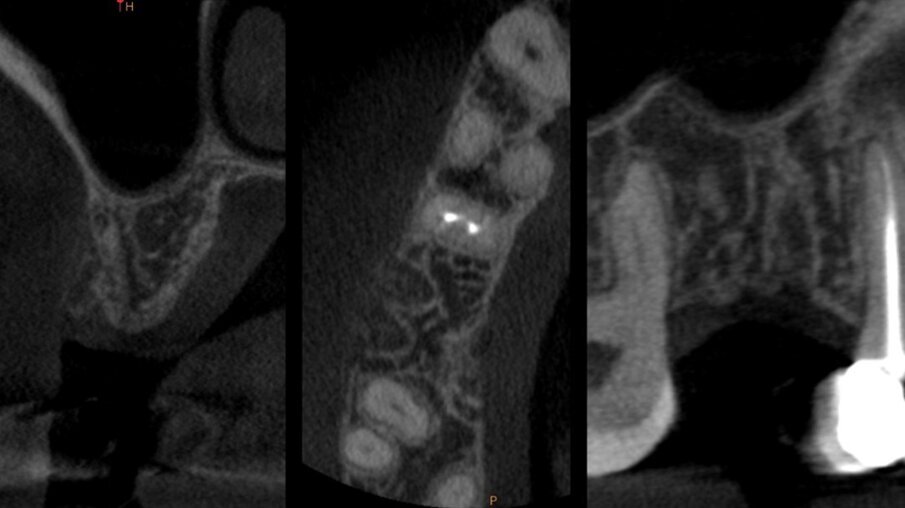

È stata eseguita una CBCT preoperatoria (Figg. 2a, 2b). La paziente, una donna di 52 anni in buona salute, ha iniziato la terapia antibiotica il giorno prima dell’estrazione con 2 gr. Amoxicillina e Acido Clavulanico. Dopo l’anestesia locale, è stata eseguita un’estrazione atraumatica cercando di non danneggiare le corticali ossee. L’alveolo è stato accuratamente pulito e risciacquato con acqua ossigenata e clorexidina 0,2% (Fig. 3). È stata praticata un’incisione intrasulculare sull’aspetto vestibolare dell’alveolo estrattivo, estendendosi al centro dei denti adiacenti. Un lembo a tutto spessore è stato sollevato ed il periostio staccato con micro-scollatori ha permesso di creare una busta per la lamina corticale (Fig. 4). La lamina corticale soft da 0,5 mm è stata prima idratata per cinque minuti in soluzione sterile e poi tagliata nella forma desiderata, tra 8 e 10 mm di altezza e con un’estensione che copre i margini mesiali e distali dell’alveolo estrattivo. La lamina corticale può essere facilmente inserita nel sito ed eventualmente ritagliata fino ad ottenerne un perfetto adattamento. I bordi devono essere rifiniti con angoli arrotondati per ridurre il rischio di perforazione e/o deiescenze sul versante vestibolare. La colla di fibrina umana (Tisseel, Baxter) è stata diluita al 10% mediante 0,9 ml di acqua bidistillata. Sulla lamina corticale sono state applicate due o tre gocce di colla, dopo di che la lamina è stata poi schiacciata con una gentile pressione digitale per adattarsi alla posizione predefinita (Fig. 5). Il lato palatale dell’alveolo è stato invece lasciato guarire per prima intenzione. Una spugna di collagene (Condress, Smith & Nephew) è stata inserita all’interno dell’alveolo per stabilizzare il coagulo ed è stata posizionata una sutura incrociata (4-0 punti di sutura in ptfe) per mantenere la spugna in posizione, le papille sono state invece suturate con due suture a fionda7 (Fig. 6). Quattro mesi dopo l’estrazione, prima di inserire l’impianto, è stata eseguita una CBCT post-operatoria per valutare la guarigione del sito operato.

Figg. 2a, 2b - CBCT pre-estrazione